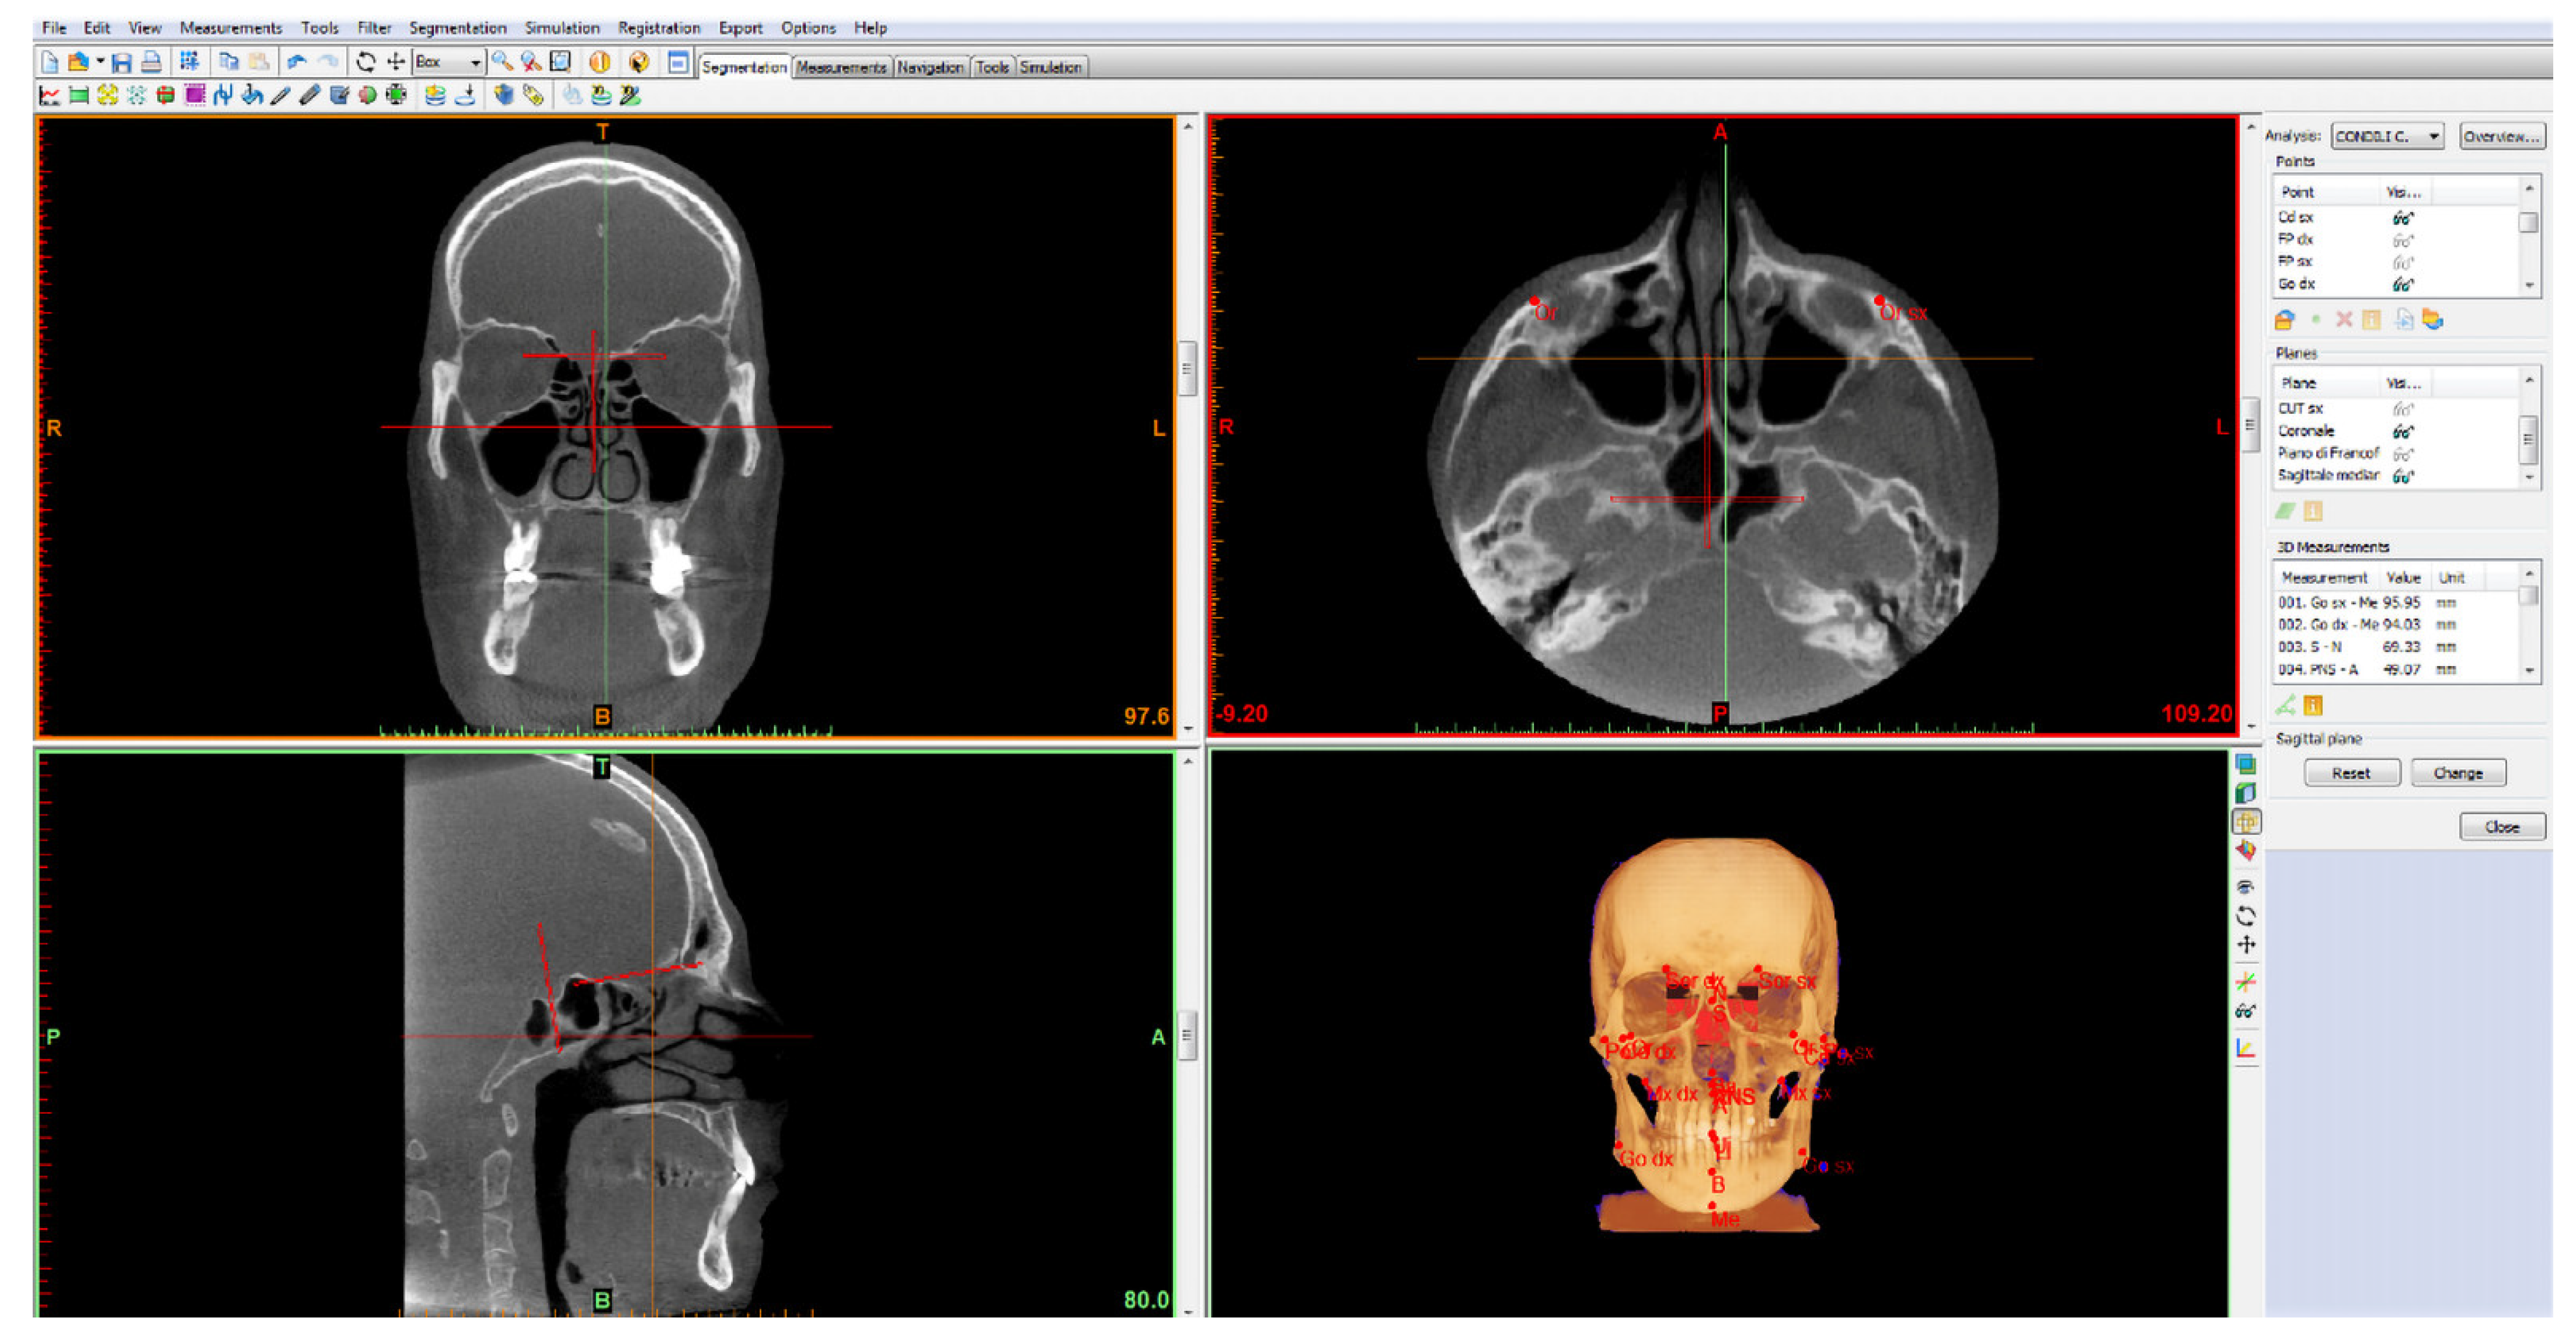

2.1. Mandibular Condylar Segmentation and Volume

- Porion point (right/left Po): highest point of the external acoustic meatus;

- Lower orbital point (right/left OR): lowest point of the orbital edge, the base of the orbital cavity;

- Pterygoid fovea point (right/left FP): most recessed point on the front face of the mandibular neck, identifiable in the three projections: axial, coronal and sagittal. It was chosen as the point that delimits the separation passage between the head and neck of the mandibular condyle.

- Frankfurt plane: calculated as the plane passing through the lower right and left orbital points (right/left OR) and from the right and left porion points (right/left Po);

- Cut plane of the right condyle (right CUT): plane passing through right FP and parallel to the Frankfurt plane;

- Cut plane of the left condyle (left CUT): plane passing through left FP and parallel to the Frankfurt plane.